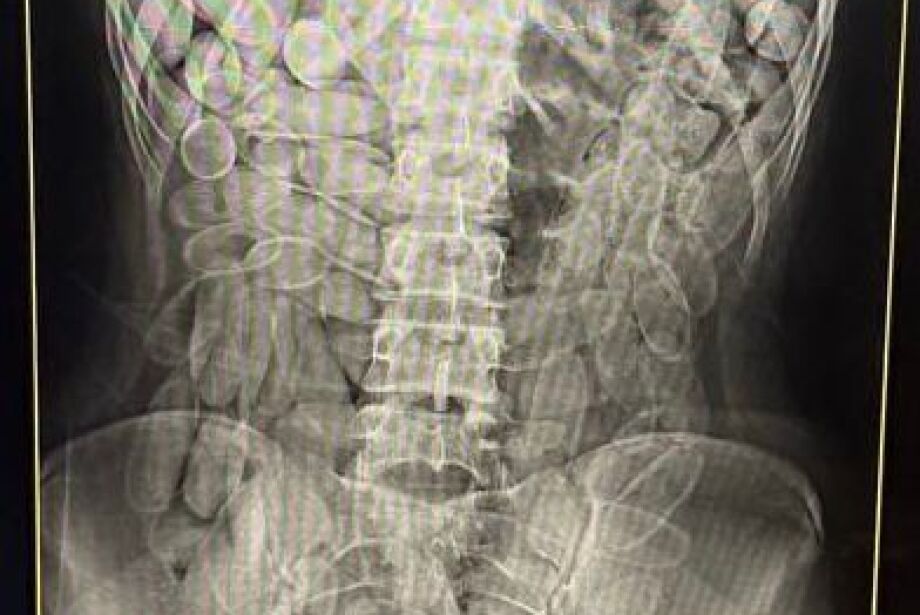

Diante da situação, ambas foram encaminhadas à Santa Casa de Corumbá, onde um exame de raio-x constatou que havia várias cápsulas do entorpecente no organismo.

Elas confessaram terem engolido, cada uma, 102 cápsulas, para fazer o trabalho de "mula", termo utilizado no caso de pessoas que transportam droga no corpo.